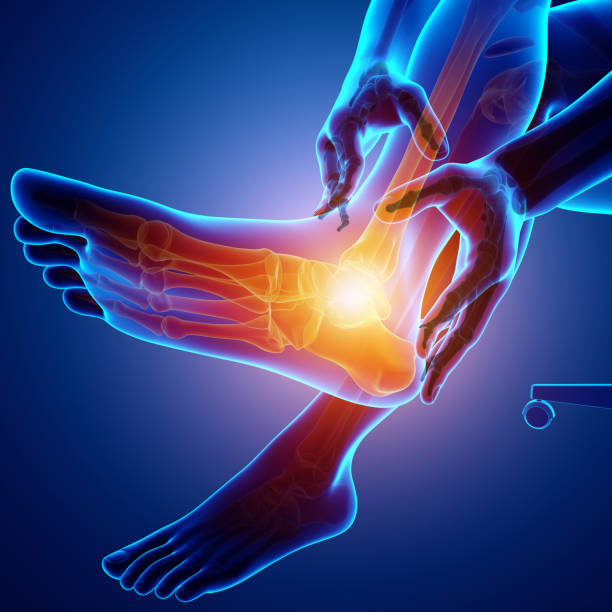

발뒤꿈치가 아픈 이유 5. 발목 터널 증후군

발뒤꿈치가 아픈 이유 다섯 번재는 발목 터널 증후군입니다. 내측 복사뼈와 발뒤꿈치 뼈 사이의 족근관을 관통하는 후경골 신경이 눌리거나 손상되면 저림, 작열감 등을 느끼게 됩니다. 이때는 신경 압박에 의한 통증이기 때문에 앞서 언급한 연조직 손상과 달리 통증의 위치가 명확하지 않고 신경 경로를 따라 퍼지는 특성을 갖고 있습니다.